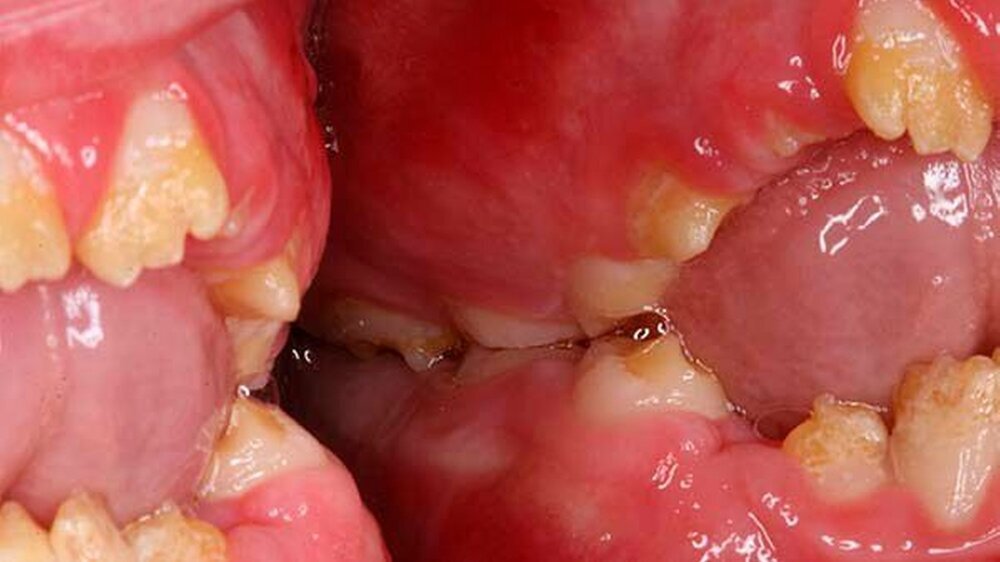

Der zehn Jahre alte Junge stellte sich an der Klinik wegen Schmerzen im ganzen Mund vor. Zusätzlich klagte der Patient über die eingeschränkte Möglichkeit Speisen ab zu beißen (Abbildung 1a und Abbildungen 3a und 3b). Die Familienanamnese ergab eine nahe verwandtschaftliche Verheiratung in der Familie. Das dentale Erscheinungsbild konnte von den Eltern des Patienten in der Verwandtschaft jedoch ausgeschlossen werden.

Der klinische Befund zeigte an beiden Dentitionen eine rauhe, zum Teil verminderte, bis fehlende Schmelzdicke und eine teilweise bräunliche Zahnverfärbung. Letztere wurden auch durch exogene Pigmenteinlagerung verursacht (Abbildung 1b und Abbildung 2).